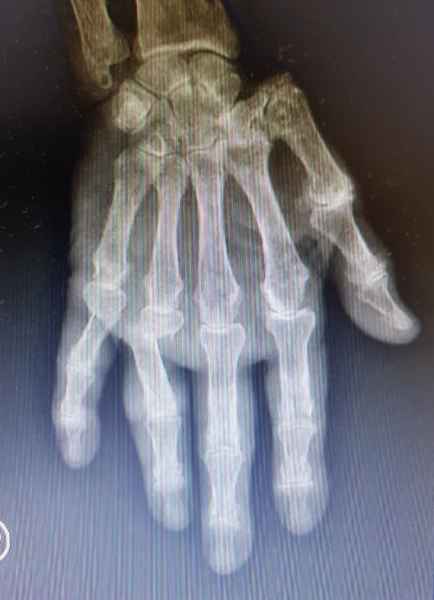

En la Artritis Reumatoidea el compromiso de las articulaciones interfalángicas proximales, metacarpofalángicas y de la muñeca estan generalemente afectadas simetricamente, lo que la distingue de la Artrosis, en la cual el compromiso se observa predominantemente en las articulaciones interfalángicas distales.

Cambios agudos como ser dolor o edema, pueden ser indicio de Artritis aguda o ataque de Gota aguda, los cambios crónicos tienden a modificar la estructura y anatomía normal de las manos como ser los dedos en cuello de cisne, mano en ventarrón, característicos de la Artritis, mientras que en la Gota crónica se observan tofos gotosos con deformidad de grandes articulaciones de la mano.

La exploración de la sensibilidad y motricidad de la mano son de utilidad en el exámen neurológico cuando se sospecha lesión de algunos de los nervios terminales del plexo braquial, dando signos característicos como son la mano en garra en la parálisis cubital, mano del mono, debido a una atrofia de la eminencia tenar debido a lesion del nervio mediano y mano péndula en la parálisis del radial.